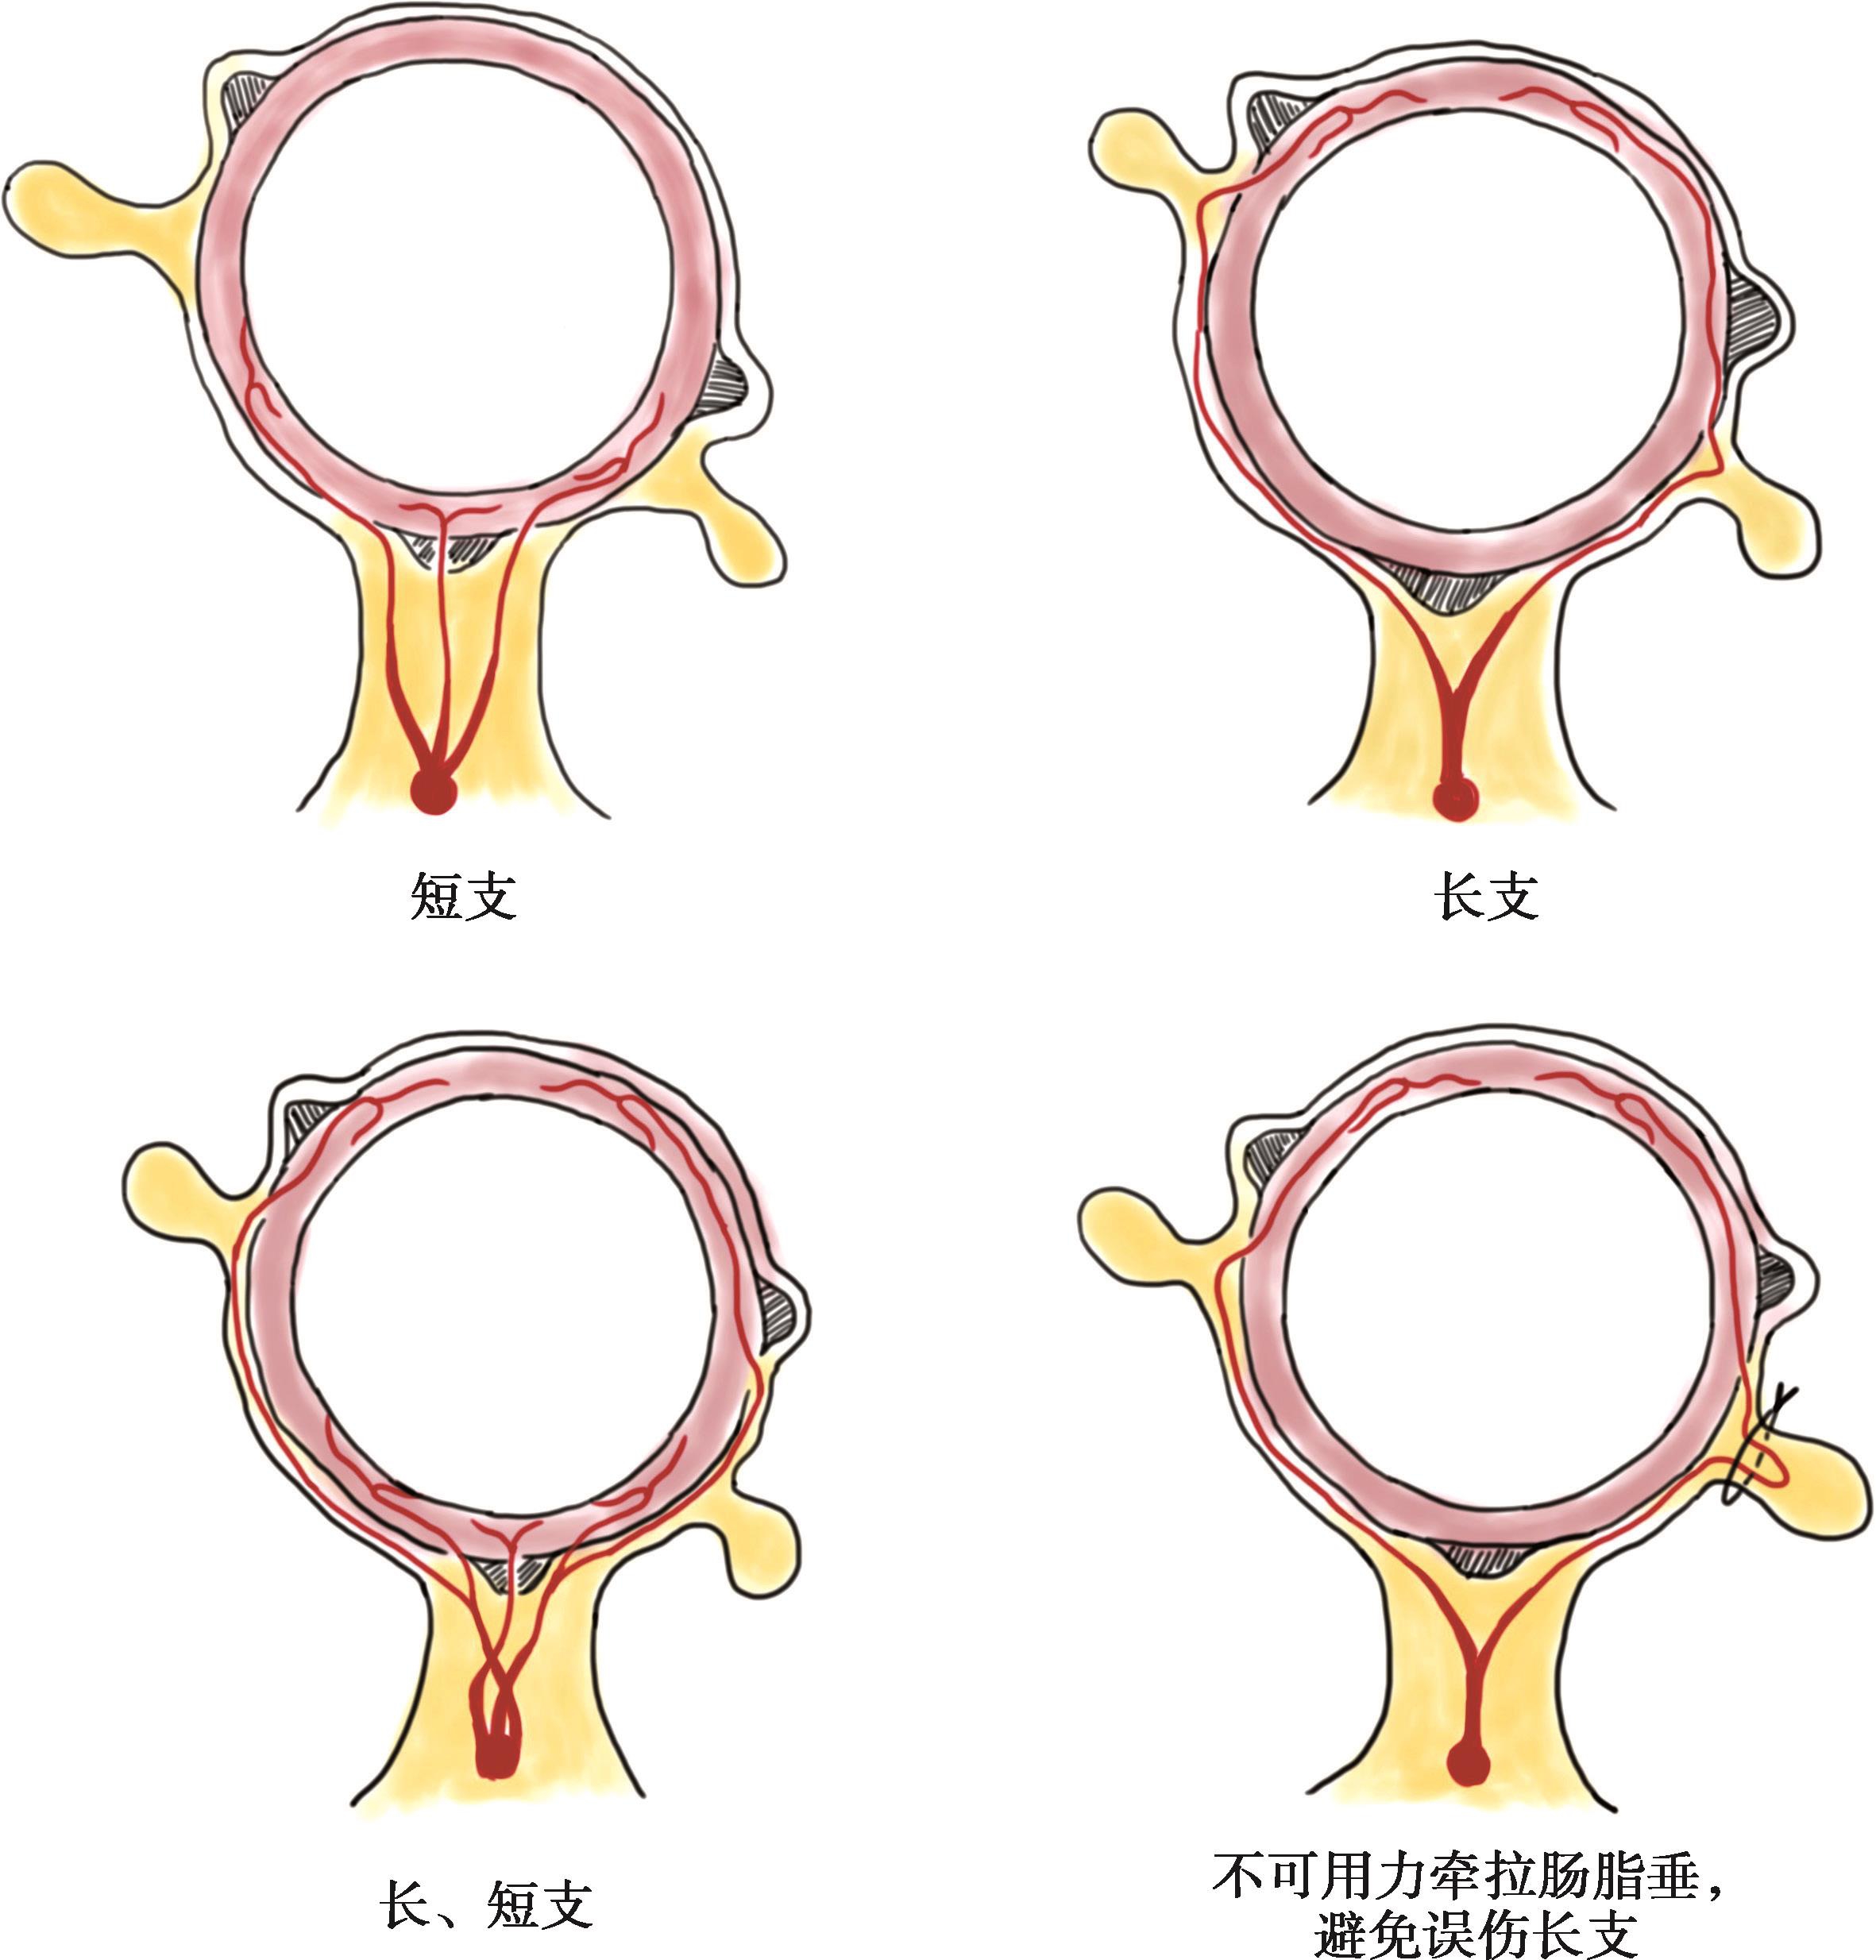

边缘动脉的终末支称直动脉,有长支和短支两种。长支在系膜缘(或结肠带)处,或在长支的起点附近又分为前后两支,沿结肠的前后面,经浆膜与肌层至对系膜缘,终支分布于对系膜面的1/3肠管,最后前后2支在独立带与网膜带之间构成血管吻合;短支起于边缘动脉或长支,一般2~3支,在系膜缘立即穿入肠壁,供应系膜面的2/3肠管(图2-6)。长支和短支共同为结肠壁的系膜面供血,而其余部分仅由长支供血,故在肠壁做纵行切口时,宜在独立带和网膜带之间进行。长支在结肠带附近分支进入肠脂垂和肠壁,手术分离肠脂垂时避免过度牵拉伤及长支主干。有报道称,损伤1支长支可使肠管坏死2.5cm。因此,结肠切除时为了保留足够的直动脉,边缘动脉应在肠管离断远端1cm处结扎。

图2-6 结肠边缘动脉